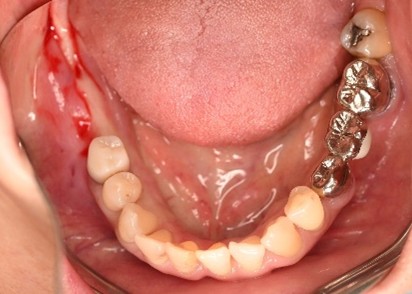

レントゲンで詳しく診てみると、左下の動いている歯、右下の一番奥は、保存することができず、抜歯しました。左下の抜歯したところは、骨造成後、左に2本、右に2本インプラントを埋入しました。

所感

左下の抜歯したところは、大きく骨が欠損していましたので、骨造成をしました。5か月間待ってからインプラントを埋入しました。骨をきちんと作ってから埋入して、正解でした。今回もX-Guideを使った埋入で、安心安全に行うことできました。

骨造成:¥55,000(税込)

インプラント4本:¥363,000×4本=¥1,452,000(税込)

ポンティック1本:¥115,500(税込)

合計:¥1,622,500(税込)

Before

赤丸は抜歯しました

【抜歯後】

【骨造成前】

【骨造成後】

After